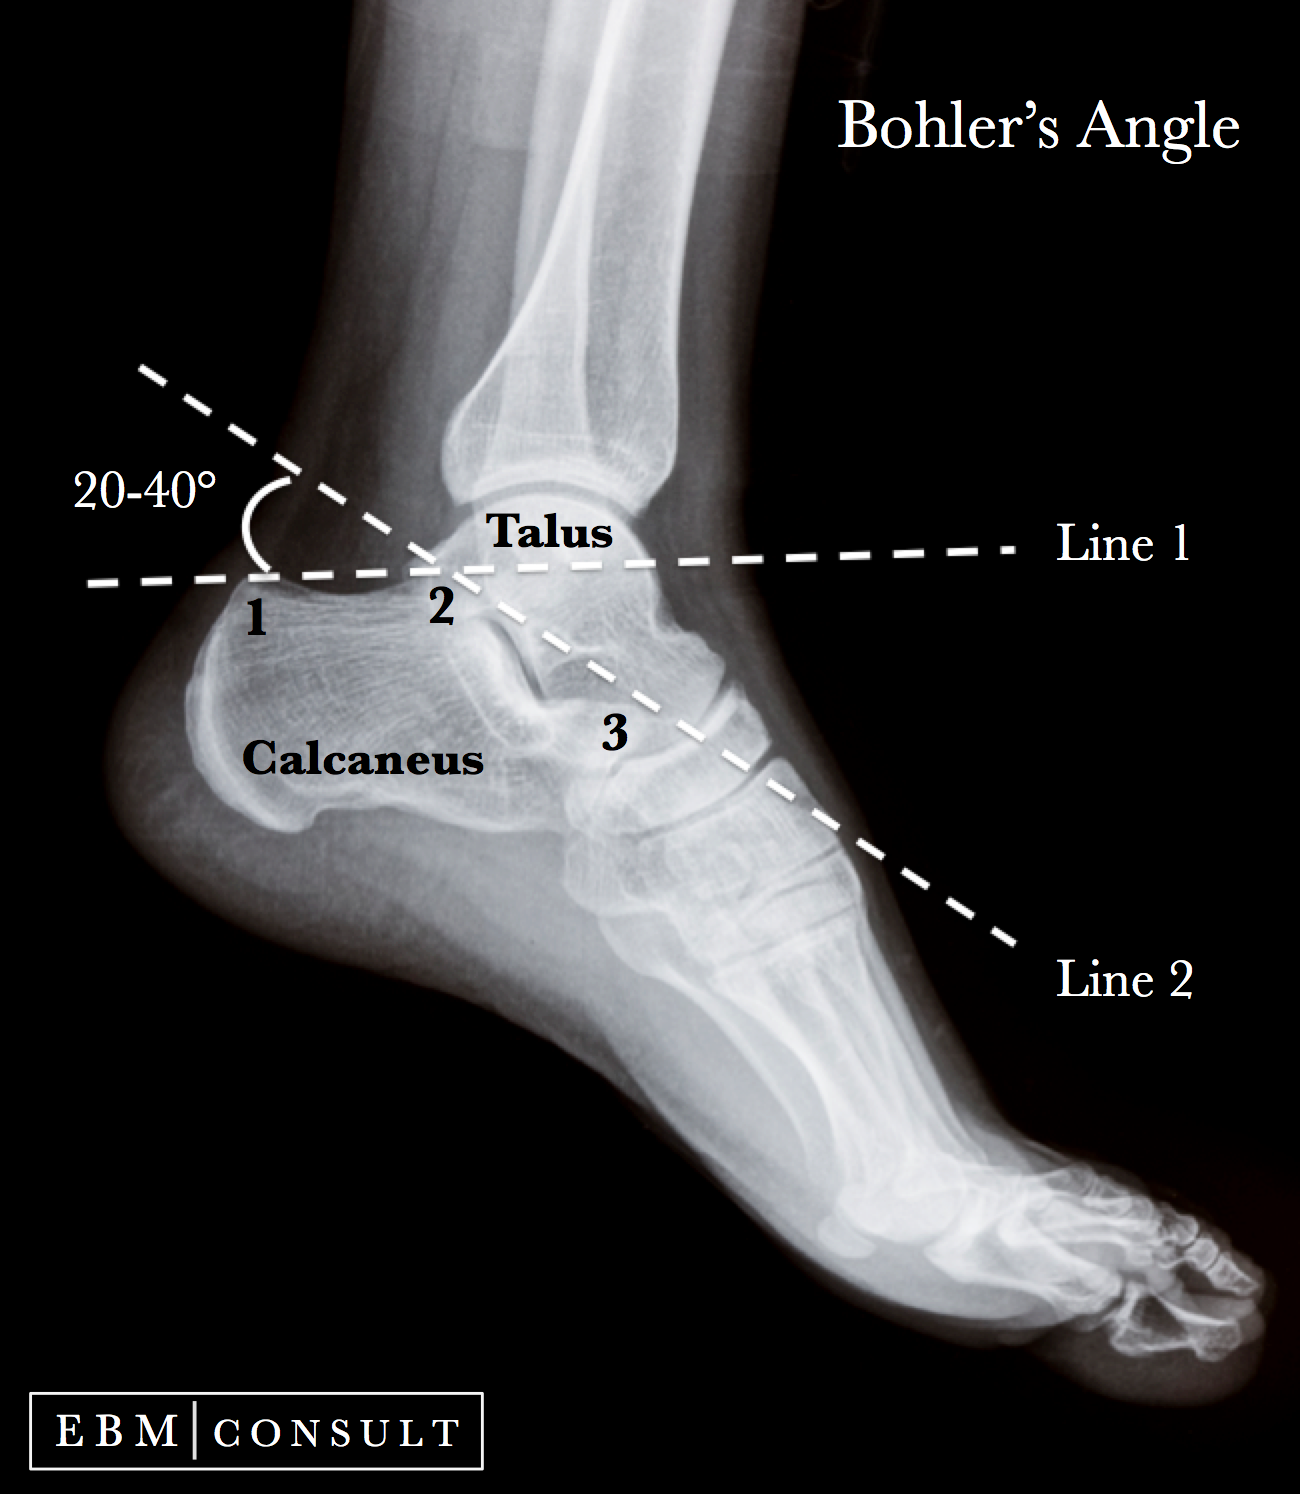

What is Boehler’s angle?

25°–45° on lateral view; used to assess calcaneal compression.